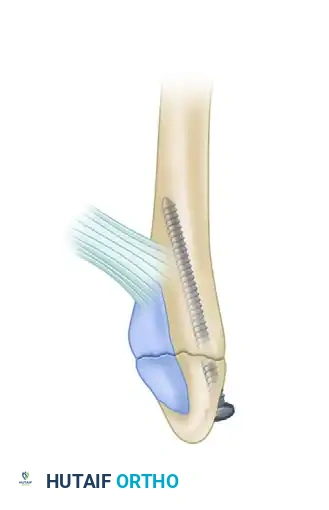

F, Minimally invasive fixation utilizing a 3.5-mm intramedullary screw.

Image

FIGURE 54-4: Fracture of the fibula above the level of the syndesmosis with disruption of the distal tibiofibular syndesmosis and rupture of the deltoid ligament. The deltoid was repaired, a small fragment plate was applied to the fibula, and the syndesmosis was repositioned and held by a transfixing screw through the distal hole of the fibular plate.